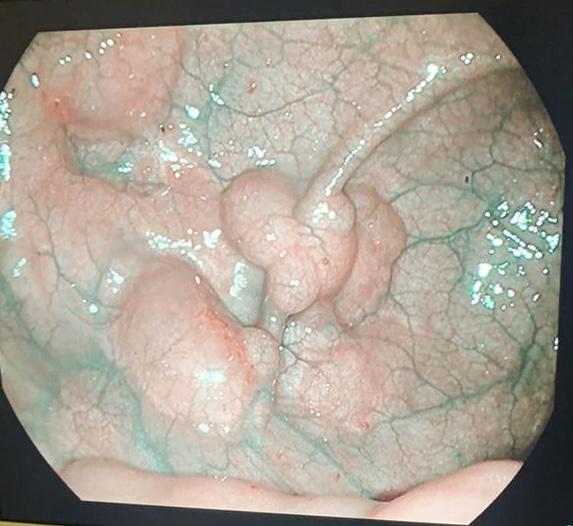

Глубокие язвы в терминальном отделе подвздошной кишки у ребенка 17 лет